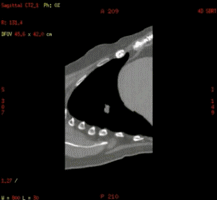

Smart D4D:胸部运动肿瘤4D成像

Smart D4D:腹部4D成像